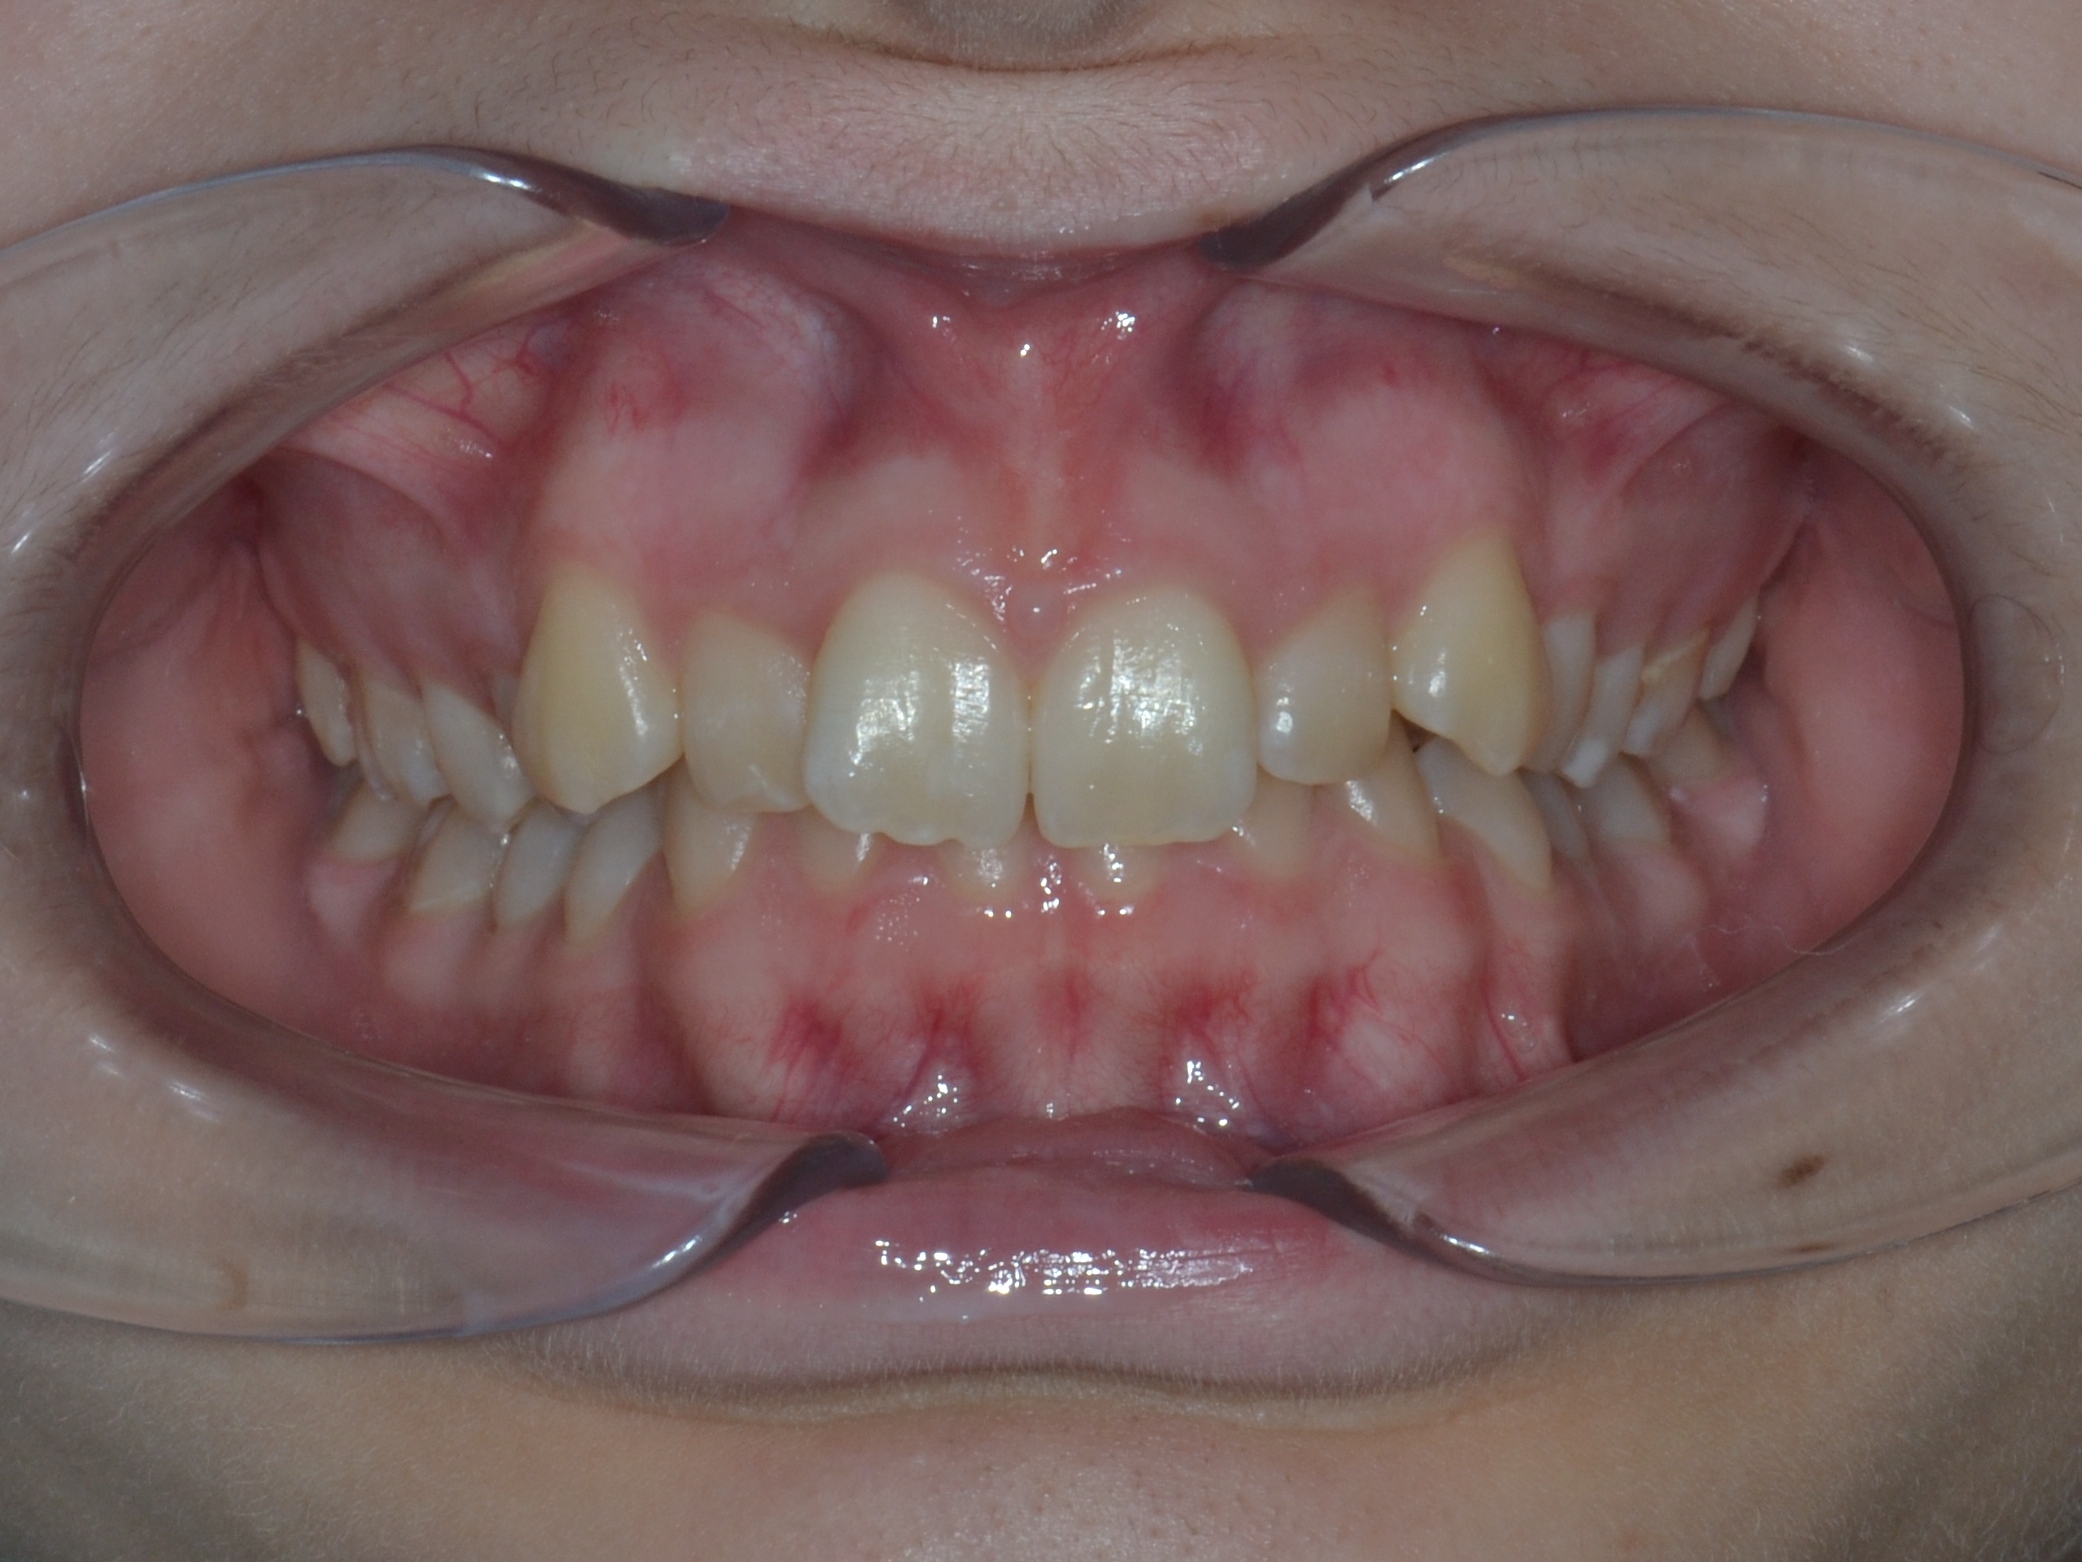

Выявленные проблемы

• Глубокое резцовое перекрытие

• Сужение верхнего и нижнего зубных рядов

• 23 зуб в щёчном положении, 22 зуб в нёбном положении с дефицитом места

• Скученное положение зубов дистальное положение и ротация нижней челюсти

• Патологическая стираемость и генерализованный пародонтит с рецессией десневого края

Брекет-система Q